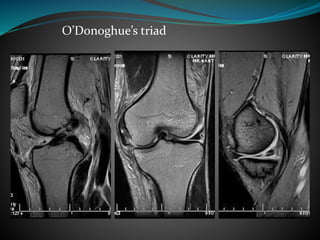

 O’Donoghue’s triad-

 ACL rupture

 MCL injury

 Medial meniscal tear

O’Donoghue’s triad